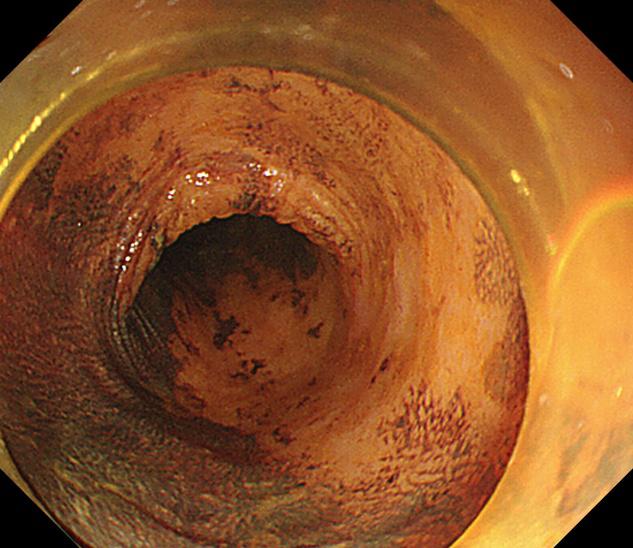

SSL(肠道锯齿状病变),多见于右侧结肠和回盲部,是大肠的癌前病变,癌变率大约10%。

内镜下观察平坦型较多,主要特征:黏液帽(黏液蛋白的缘故)、云雾状外观、扩张的II型腺管(Open II型)、分支扩张、蛇形的血管。当病变出现有蒂或亚蒂、隆起中有隆起、中央明显凹陷、病灶明显发红、合并IIIL、IV、Vi、VN型腺管表现时应想到癌变的可能性。